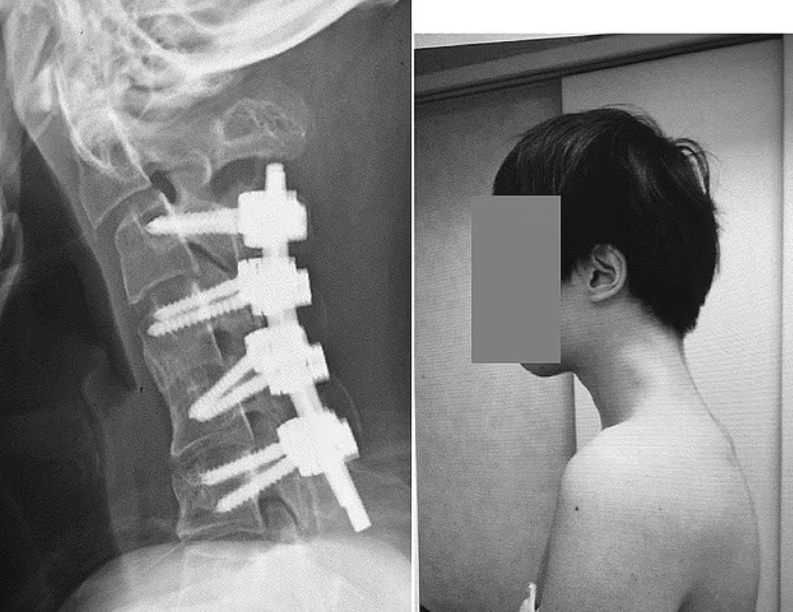

수술을 통해 의료진은 남성의 목뼈에 나사와 금속 막대를 삽입해 자세를 교정했다. 수술 6개월 후 그는 머리를 수평으로 들어올릴 수 있게 됐고, 1년 뒤 추적 검사에서도 머리 들어올리거나 음식을 삼키는 것과 관련된 증상이 재발하지 않았다.

|

| 스마트폰으로 하루에 몇 시간씩 게임을 하던 20대 남성이 ‘머리떨굼 증후군’ 진단을 받았다. 목뼈에 나사와 금속 막대를 삽입해 자세를 교정한 모습. [데일리 메일] |